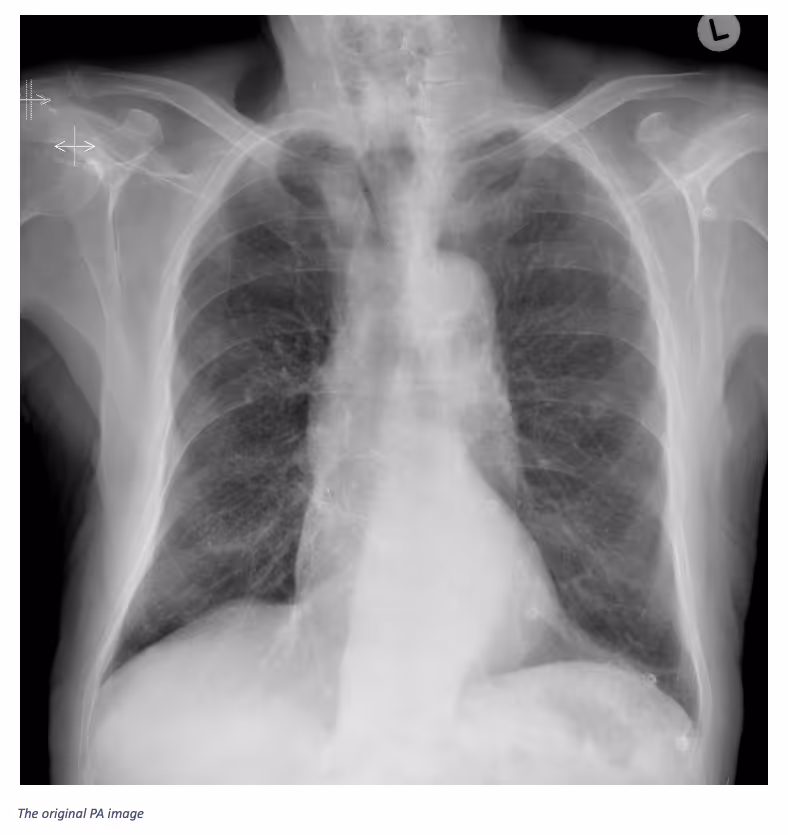

Ferrum Health partners with best-in-class AI providers offering solutions designed to reduce radiology workload and improve patient care.VinBrain Case Study: Distinguishing Lung Nodule from Other Easily Confused LesionsIntroductionConfusion in distinguishing between similar-looking findings on x-ray images is a problem that can be encountered by physicians (e.g., sclerotic rib lesions can mimic pulmonary nodules). The key is to look at prior radiographs. If the nodule remains projected over exactly the same rib site despite projectional differences then the physician can be confident that the lesions are within the rib rather than the lung.Clinical CaseAn 85-year-old male patient presented to the hospital with “Recent TAVI (transcatheter aortic valve implantation). A chest x-ray was required with both AP and PA views, then CT. After screening these images, a nodule was projected in the left mid-zone. The nodule “moves'' relative to the lung but remains directly associated with the anterior aspect of the left fourth rib on both the PA and AP projections. This indicated that the lesion is associated with the rib, which was confirmed by looking at the patient’s prior TAVI planning CT. Finally, based on CT images, the physician confirmed the Sclerotic lesion within the anterior aspect of the left 4th rib.